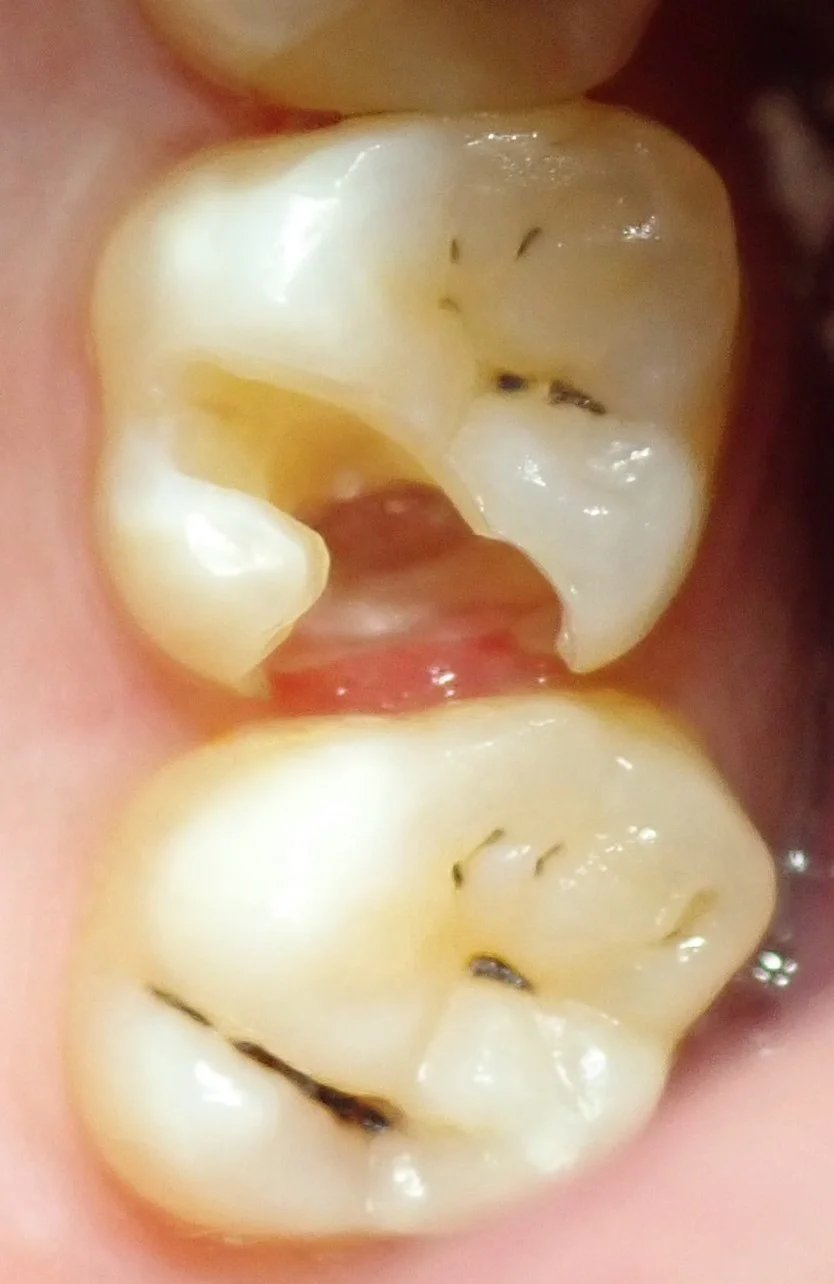

さて、では写真の方を。

まずは術前ですね。

お隣の県にて開業されている歯科医師の方です。

昔詰められた保険の白い詰め物が、大きく欠けて、中で虫歯になっているのが分かります。

そして、虫歯を取りきった写真がこちらです。

神経がうっすら見えかかるほどの大きなサイズでした。

歯が残っているように見えますが、実際は中の方はほとんど残っておらず・・・

後ろ半分は表面のエナメル質だけ残っているっていう状況になってしまっています。

ダイレクトボンディングで処置しなかった場合、この歯は多くの先生で被せ物に近い形態になってしまうと思います。

一気に歯の寿命を縮めてしまうので、ここでダイレクトボンディングのメリットが活かされてきますね。